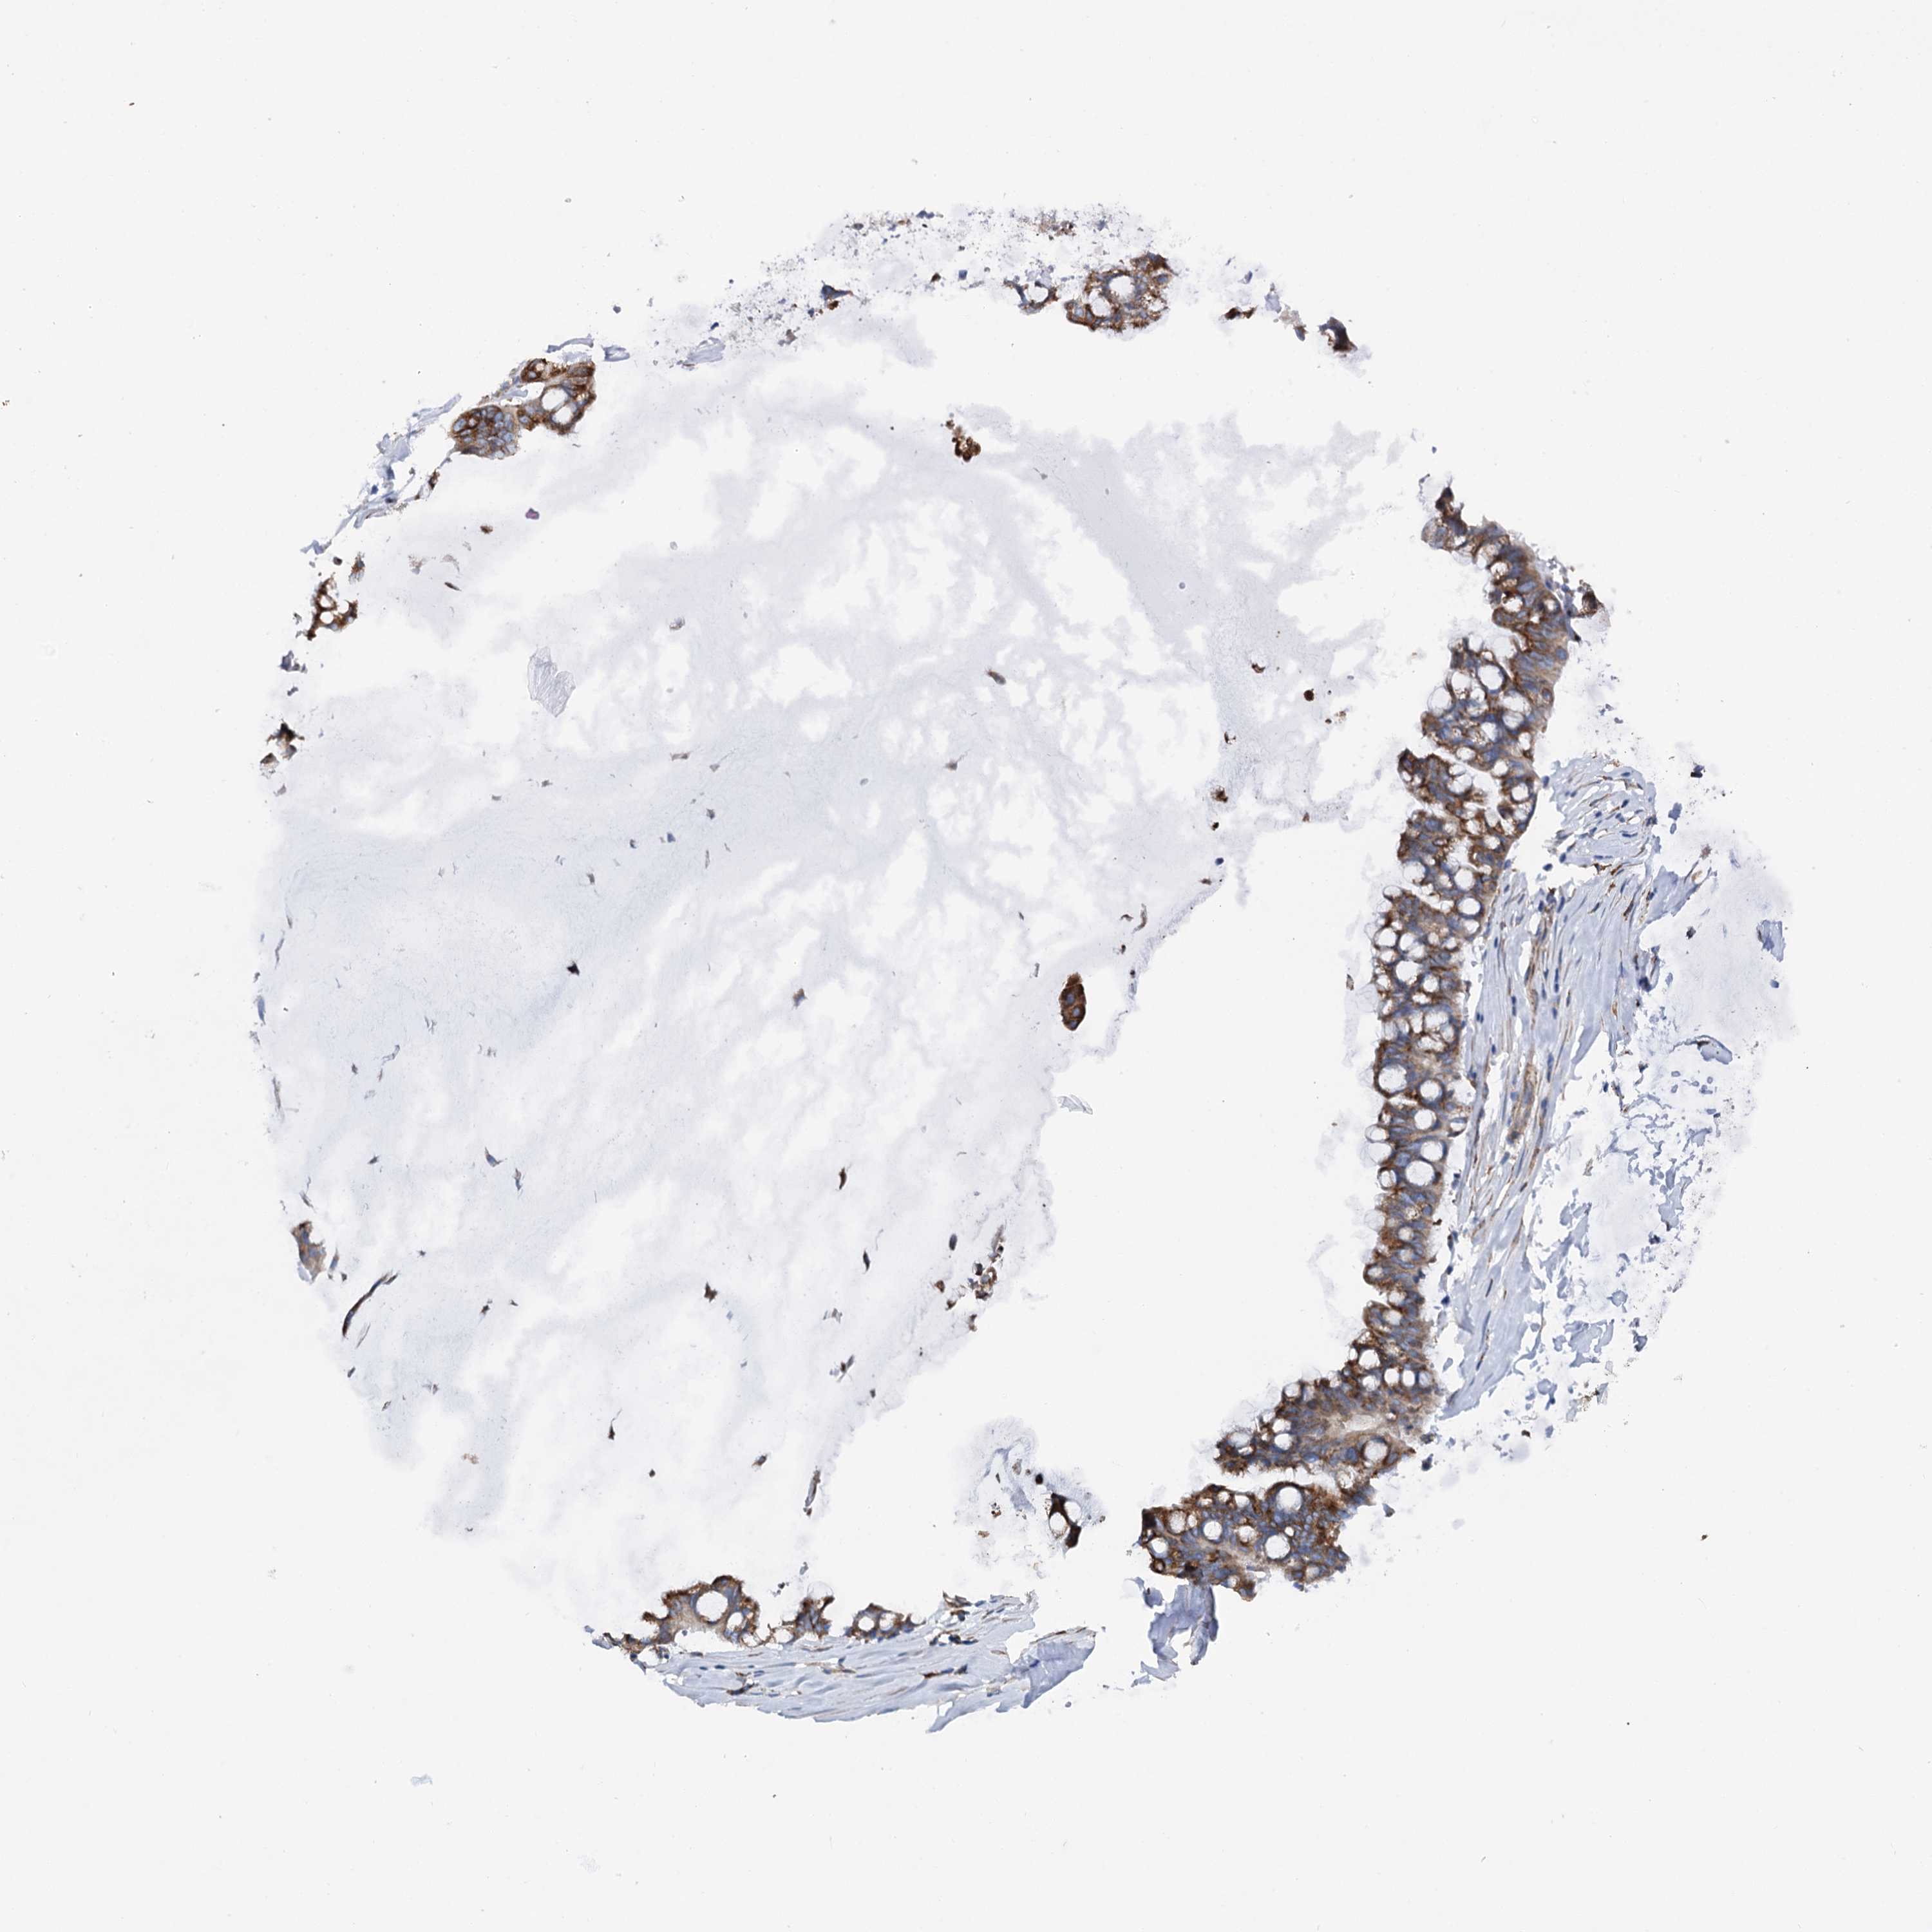

OVARIAN CANCER - Protein expressioni

A mouse-over function shows sample information and annotation data. Click on an image to view it in a full screen mode. Samples can be filtered based on level of antibody staining by selecting one or several of the following categories: high, medium, low and not detected. The assay and annotation is described here.

Note that samples used for immunohistochemistry by the Human Protein Atlas do not correspond to samples in the TCGA dataset.

Antibody stainingi

Antibody staining in the annotated cell types in the current human tissue is reported as not detected, low, medium, or high, based on conventional immunohistochemistry profiling in selected tissues. This score is based on the combination of the staining intensity and fraction of stained cells.

Each image is clickable and will lead to virtual microscopy that enables deeper exploration of all samples and also displays staining intensity scores, fraction scores and subcellular localization as well as patient and tissue information for each sample.

Antibody HPA037417

Staining

High

Medium

Low

Not detected

Intensity

Strong

Moderate

Weak

Negative

Quantity

>75%

75%-25%

<25%

None

Location

Nuclear

Cytoplasmic/membranous

Cytoplasmic/membranous,nuclear

Cystadenocarcinoma, serous, NOS

Carcinoma, endometroid

Cystadenocarcinoma, mucinous, NOS

Carcinoma, NOS